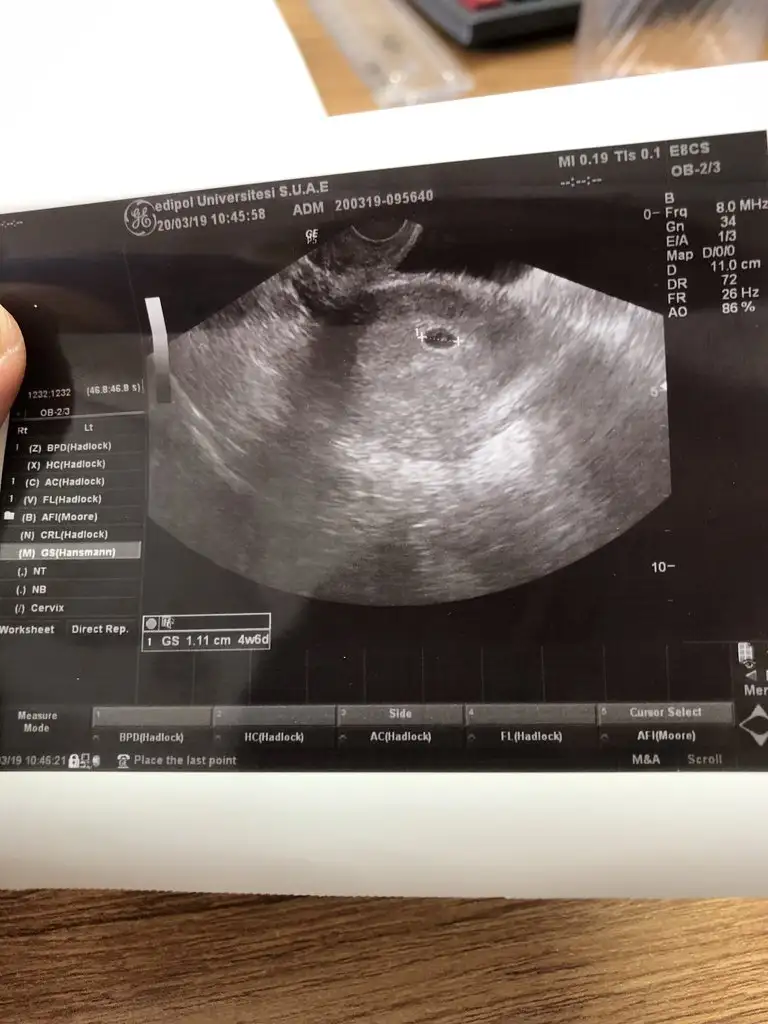

Adetime 12 gün kala tesr yapmaya başladım tabiki negatifti sonra acile gittim beta 1.4 dü sonra bir hafta geçti adetime 7 gün varken Erken gebelik testiyle öğrendim silik cıktı havalara uctum sonra en son adetime bir gün kala acile tekrar gidip kan verdim betahcg 677.8 cıktı 4 haftalık olduğumuzu öğrendim :))) iki sorum var kızlar Bu değer normalmi biraZ daha bekleyip doktora oyle gidiyimde keseyi göreyim diye beklıyorum yalnışmı yapıyorum